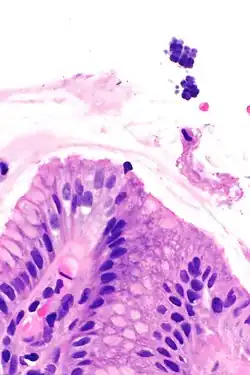

| Gastric mucosa and Sarcina on upper right. H&E stain. | |